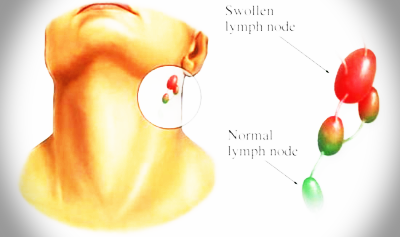

임파선염이란?

임파선염은 임파선이 비대해지거나 임파선에 염증 반응이 일어나는 증상이다. 대부분 특별한 치료가 필요하지 않은 양성이거나 일시적인 바이러스 감염증 등에 의한 경우가 많다. 일부에서는 치료가 필요한 결핵이나 악성종양에 의한 임파선염인 경우도 있다.

사람의 몸에는 온 몸을 작은 관으로 연결하는 혈관과 비슷한 구조의 임파선이 있다. 임파선은 혈액 이외의 체액이 이동하는 통로가 된다. 임파선은 도로에서 교차로에 해당하는 부분에 임파절(lymph node)이라는 구조를 갖고 있다. 정상적인 경우 임파선은 손으로 만져지지 않지만, 임파절은 만져지는 경우가 많고 특히 어린 아이들에게서는 대부분 뚜렷하게 느껴진다. 임파선염이라고 하면 보통 임파절이 커져있는 상태를 말한다. 임파선은 우리 몸의 면역체계와 관련이 있어 외부에서 균이 들어오면 이에 반응하기 위해서 붓기도 하지만, 오히려 병이 이 통로를 타고 퍼지는 경우도 있다.

따라서 임파선염이 우리 몸의 정상적인 면역반응으로 인해 나타나는 증상일 경우에는 특별한 조치가 필요 없지만, 다른 병이 이 통로를 통해 퍼지면서 생기는 현상이라면 그 원인에 대한 적절한 진단과 치료가 필요하다. 임파선염의 원인은 구강을 비롯한 상부호흡기계의 감염증에 의해서 발생하는 경우가 많다. 감염의 원인으로는 연쇄상구균, 포도상구균과 같은 세균이나 바이러스 감염이 있을 수 있다.

임파선염의 증상으로는 임파선이 비대해져서 종괴(덩어리)가 만져지거나, 감염증에 의한 임파선염의 경우에는 눌렀을 때 아픈 경우가 많다. 종괴를 덮고 있는 피부에 발작이 동반될 수 있다.